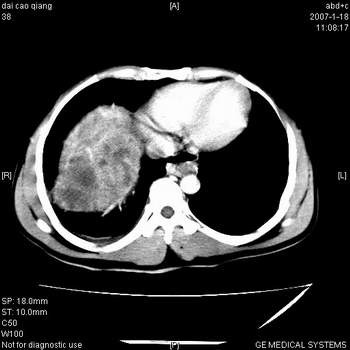

肝右叶巨块型肝癌,伴癌栓形成.

符合巨块型肝癌表现:

1、平扫低密度,增强后表现为快进快出。

2、动脉期可见迂曲的动脉供血血管

3、并可见门静脉右支癌栓形成

4、可见假包膜

5、腹主动脉旁结节影,考虑肿大淋巴结。

典型的肝右叶巨块型肝癌破裂、门脉瘤栓形成。

肝右叶巨大不均匀低密度肿块,前缘有假包膜,增强明显的呈快进快出表现,门脉右支有癌栓,病人虽然年轻但还是首先考虑肝右叶巨块形肝癌,病人血象高只能说有合并感染。不支持肝脓肿。